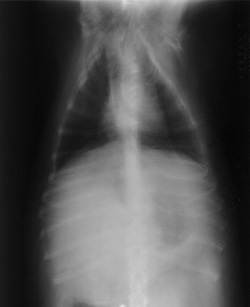

Double Exposures